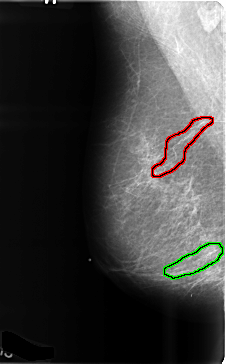

B_3470_1.LEFT_MLO

FILE: B_3470_1.RIGHT_MLO.OVERLAY

TOTAL_ABNORMALITIES 2

ABNORMALITY 1

LESION_TYPE CALCIFICATION TYPE VASCULAR DISTRIBUTION N/A

ASSESSMENT 2

SUBTLETY 5

PATHOLOGY BENIGN_WITHOUT_CALLBACK

TOTAL_OUTLINES 1

BOUNDARY

ABNORMALITY 2